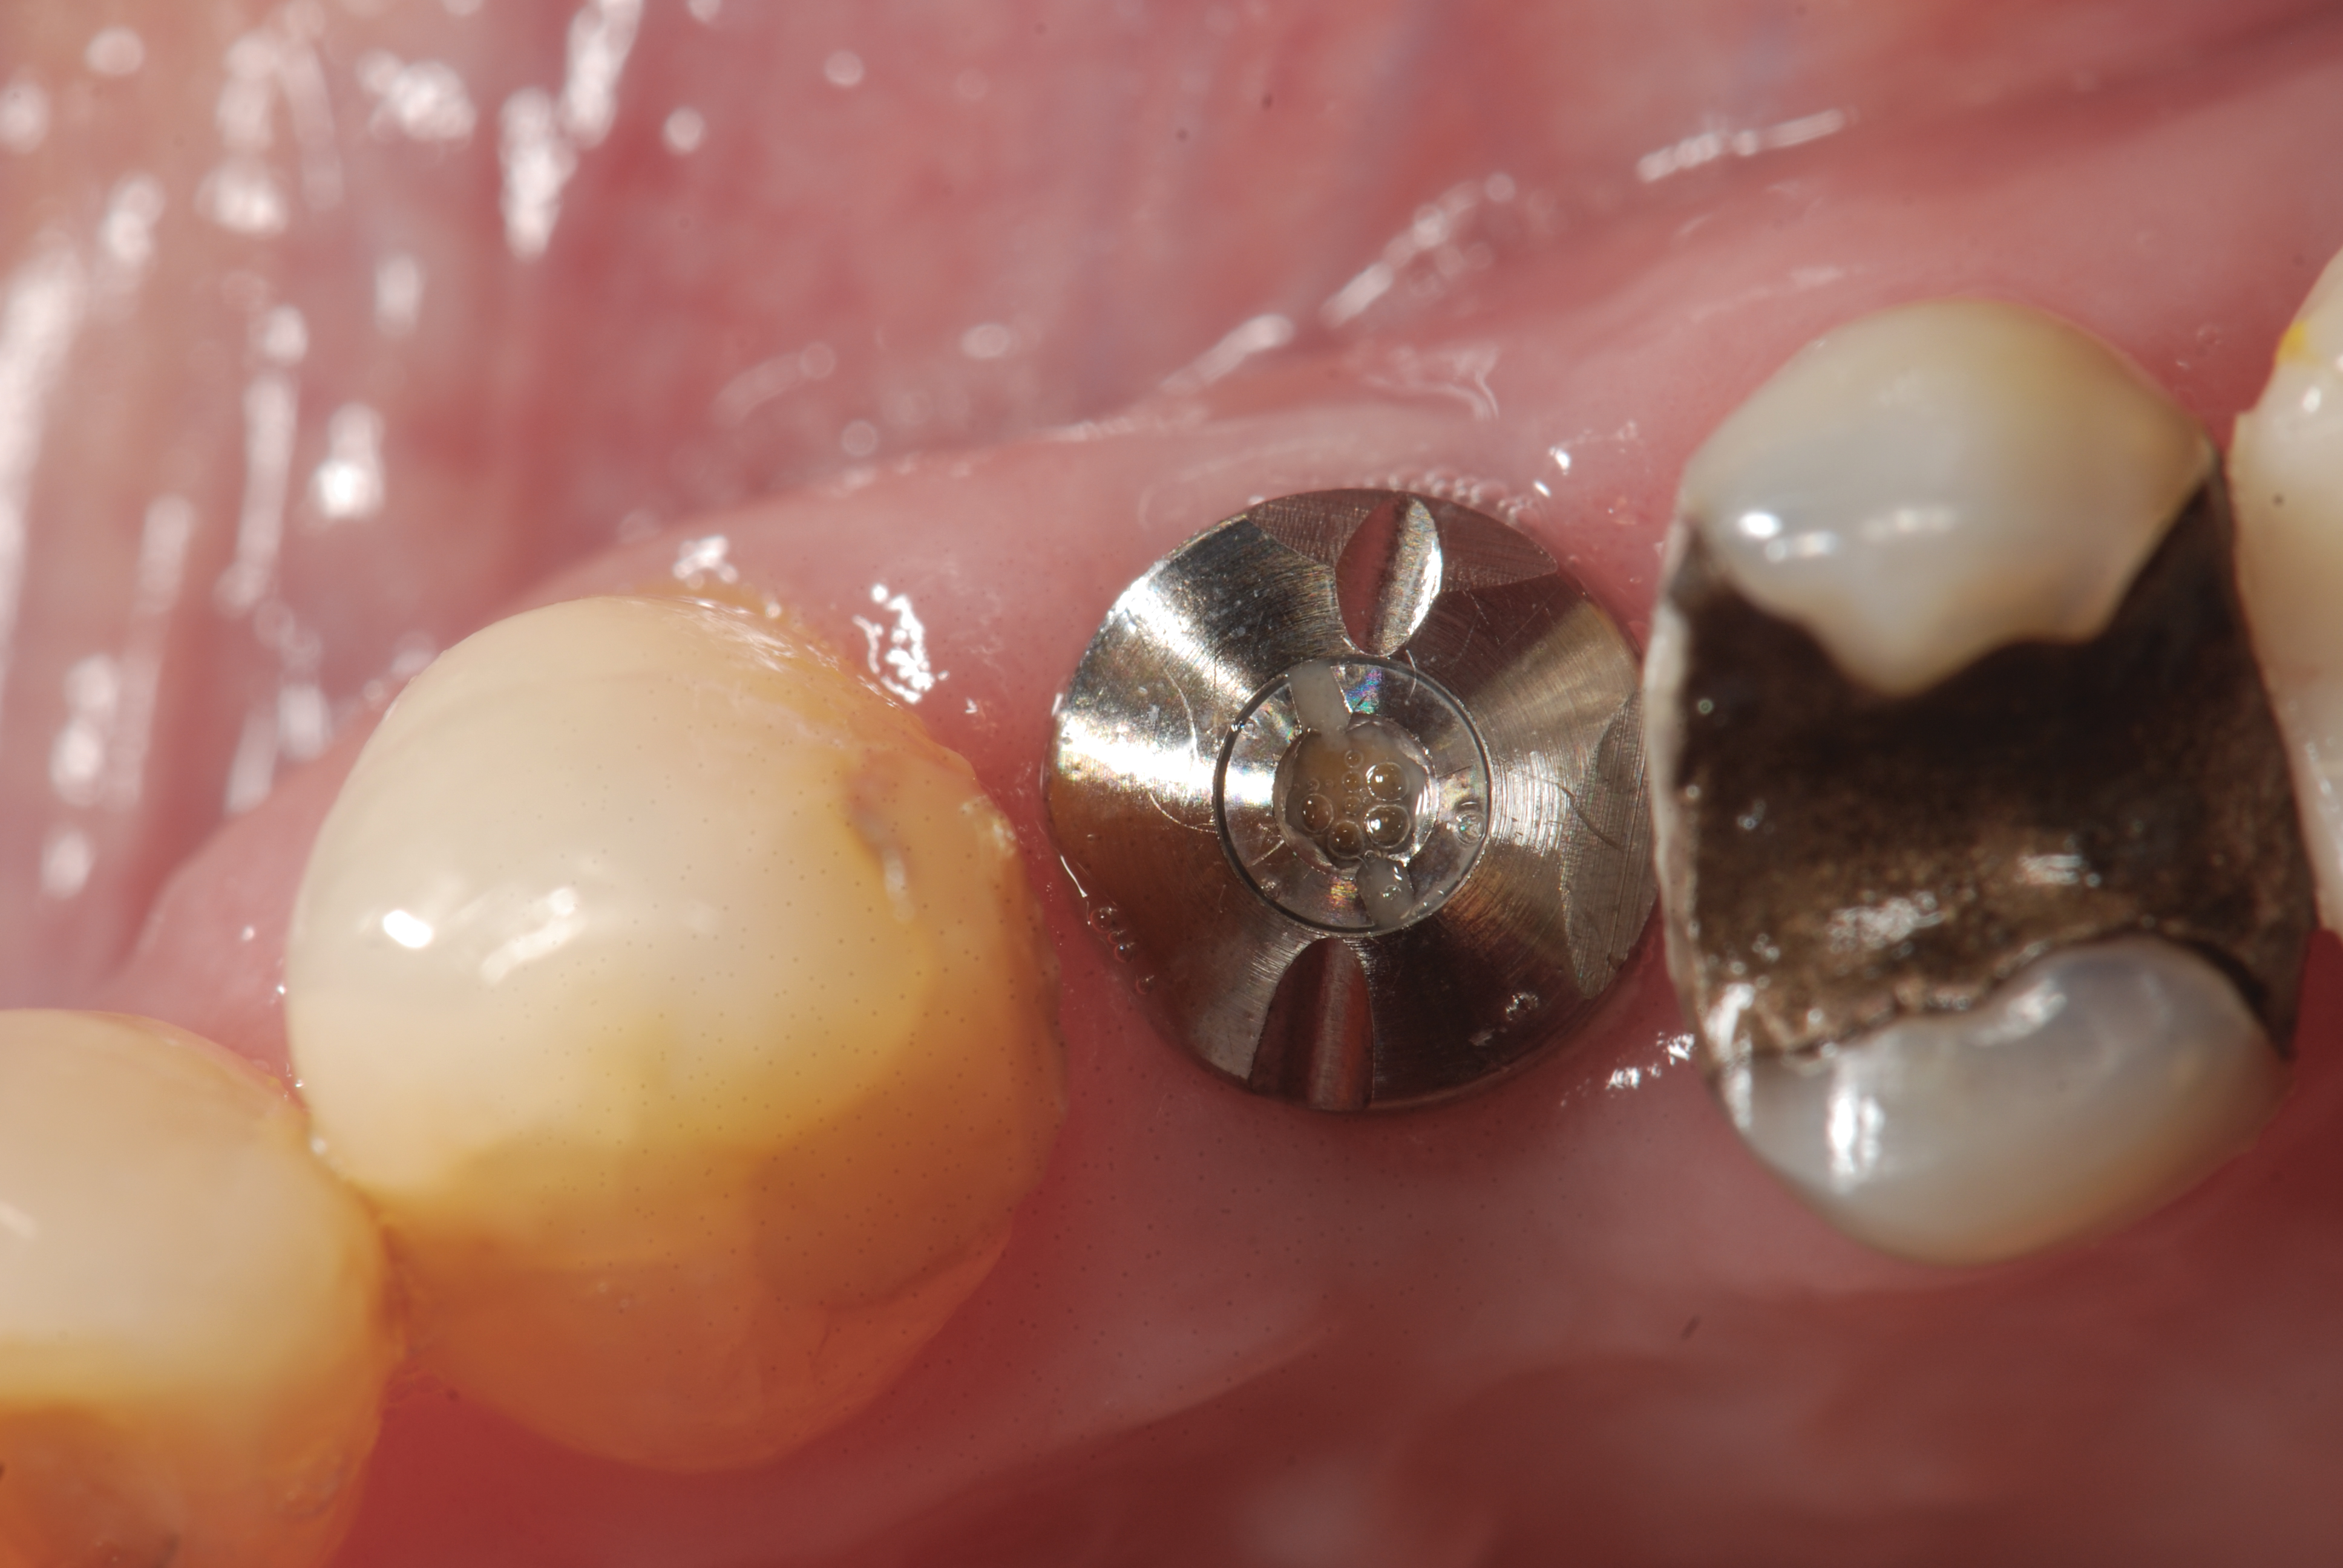

Furthermore, consider that after placing implants, oral surgeons and/or periodontists perform a surgical release to verify healing—usually 3 to 4 months post-treatment—to ensure the patient can proceed with restorative therapy.15 During this appointment, the specialist can use an IOS system and scan the now integrated implant with a corresponding scanbody in place to provide relevant impression and opposing-arch/occlusion data to the restorative dentist and laboratory, thereby relieving the patient of the need for an impression appointment with the restorative dentist.16,17

This workflow would involve the surgeon using a scan-ready healing abutment or removing the healing abutment, placing a scanbody on the implant, and scanning it using an IOS. This significantly streamlines the process for all parties involved. Previously, impressing for dental implant restorations required the use of conventional impression materials and impression copings, a time-consuming effort fraught with the potential for errors.18

Fig 4. When surgical specialists use IOS following implant healing (Fig 4) with corresponding scanbodies (Fig 5), intraoral impression scans of the patient’s postoperative condition can be acquired and shared with the restorative dentist and laboratory (Fig 6).

Figure 4